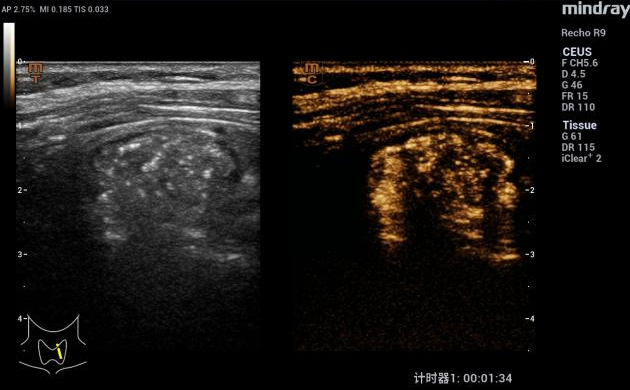

为进一步确认,程主任让刘阿姨喝下“一杯水(在400ml普通饮用水里只加了6滴造影剂)”。屏幕上清晰地显示:水流直接流入了那个“团块”里面!还发现“团块”靠近食管的部位有个小缺口。

饮造影水94秒